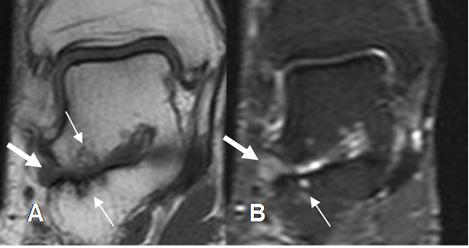

Fig 109. Sindrome del seno del tarso.

A: RM coronal en T1 y B: RM coronal en STIR. Lesiones osteocondrales en la articulación subtalar, (Flechas delgadas), con extensión de los cambios inflamatorios a la grasa del seno del tarso. (Flechas gruesas).